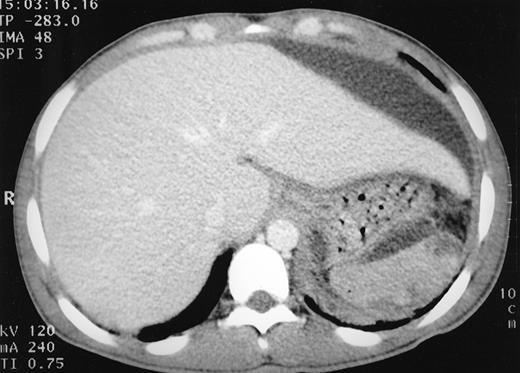

A 21-year-old man with homozygous sickle cell disease presented with a 3-week history of epigastric pain, anorexia, and weight loss of 5 kg. On examination he was in considerable discomfort and was febrile (temperature 38.5°C) and tachycardic (110 beats per minute [bpm]). Lung fields were clear, oxygen saturation was 100% on air. The liver was enlarged to 6 cm below the costal margin with tenderness over the left lobe. Blood count revealed a hemoglobin level of 7.3 g/dL (2 g/dL below his steady-state value) and marked neutrophilia (46.0 × 109/L) with left-shift. Liver function tests showed moderate elevation in gamma-glutamyl transferase (200 IU/L; normal range, 5 to 55 IU/L) but were otherwise unremarkable. Differential diagnosis for such a presentation in sickle cell disease includes hepatic sequestration, cholecystitis, and mesenteric sickling crisis. The patient was treated with analgesics, intravenous broad spectrum antibiotics, and exchange blood transfusion. Ultrasound and computed tomography (CT) abdomen showed a subcapsular fluid collection 10 cm in diameter related to the left lobe of the liver, with no evident intrahepatic, biliary, or splenic pathology (Fig 1). On percutaneous aspiration 250 mL pus was obtained. Microscopy showed yeasts and polymorphonuclear leukocytes, and Candida albicans was isolated from pus and blood cultures. He was treated with intravenous fluconazole and percutaneous drainage of abscess using an indwelling pigtail catheter. A total of 1.5 L of pus was drained over a 4-week period until no fluid remained. He has since remained well, with no recurrence of the abscess.

CT scan of abdomen showing a large subcapsular collection of fluid compressing the left lobe of the liver. Liver and spleen appear normal.

CT scan of abdomen showing a large subcapsular collection of fluid compressing the left lobe of the liver. Liver and spleen appear normal.